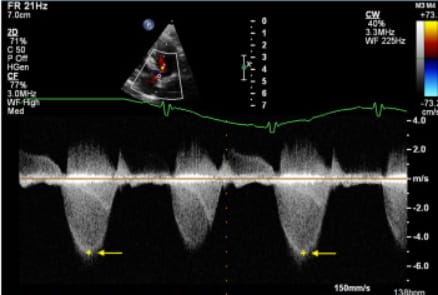

Representative spectral Doppler echocardiographic image taken from a dog with pulmonary valve stenosis, illustrating the modal (‘chin’) velocity method used to identify peak instantaneous transpulmonary velocity in the present study. The yellow ‘+’ and arrow denote modal velocity.